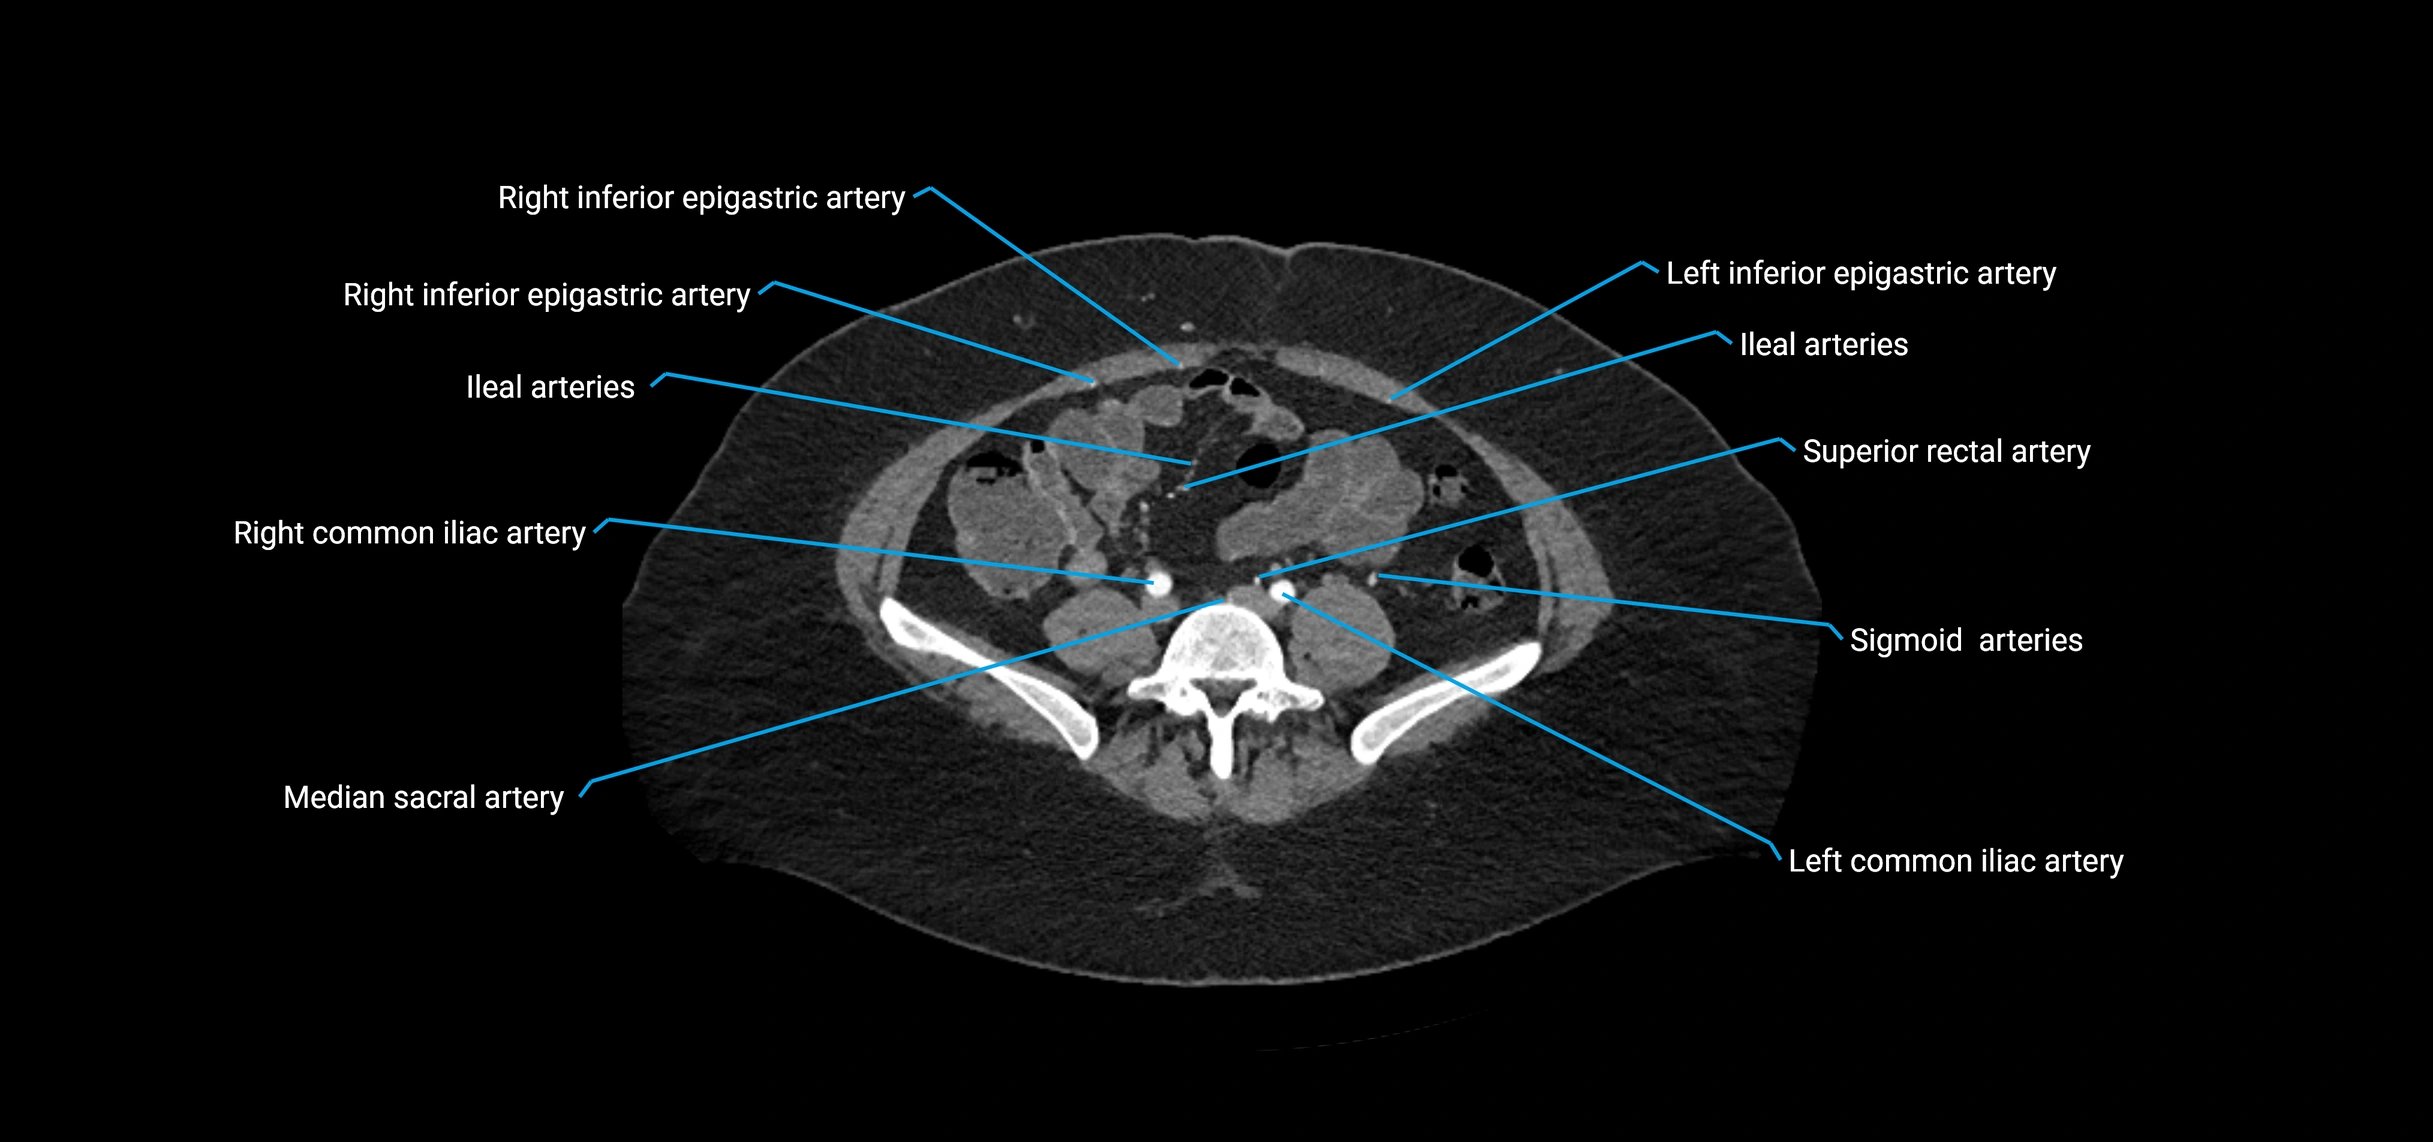

Contrast-enhanced CT (CTA):

• Gold standard for abdominal aortic imaging

• Provides excellent detail of lumen, wall, aneurysm, thrombus, and branch vessels

• Multiplanar and 3D reconstructions help in aneurysm measurement, stent graft planning, and dissection evaluation